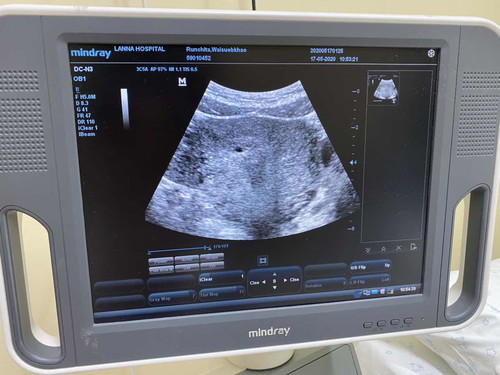

ของหนูก้เป็นตอนอัลต้าซาวครั้งแรกก้เจอเจอแต่ถุงตั้งครรภ์ หมอเลยนัดไปอัลต้าซาวครั้งที่2 เจอน้องค่ะ ตอนนี้ 6w6d นัดคลอด8มกราคม63 ค่ะ

ปัยซาวมาเมื่อวาน6w2dเจอแต่ถุงตั้งครรภ์ยังม่เจอตัวน้องเหมือนกันคะ.หมอนัดอีกที10wคลอด10มค.คะ

ใช่ค่ะ เราไป 12ที่ผ่านมาเจอแต่ถุง 6w2d วันค่ะ นัดอีก2อาทิต

5 มกราซาวตอน 6 week 3 day เจอถุงตั้งครรภ์ เจอน้องและหัวใจกระพริบๆค่ะ น้องขนาด 9.1 มิลลิเมตร